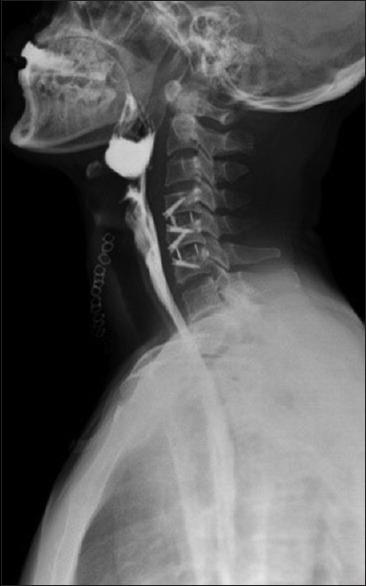

Cervical osteophytes may be seen in diffuse idiopathic skeletal hyperostosis, ankylosing spondylitis, posttraumatic, postoperative, degenerative causes, cervical spondylosis, and infectious spondylitis. A cervical osteophyte is very rarely considered among the differentials for symptoms of dysphagia. C5-C6 as well as C6-C7 being a site of greater load-bearing and mobility, the propensity to form osteophytes is high, with a small osteophyte leading to local mass effect. A 42-year-old male patient presented with mild dyspnea and significant dysphagia since 8 months, accompanied by dysphonia, weight loss, and intermittent aspiration. Clinical examination including neurological examination was normal. A barium swallow showed that osteophytes were severely protruding and displacing the lower pharynx and the proximal esophagus anterosuperiorly. The patient underwent surgical removal of the osteophyte through Smith-Robinson approach. Complaints of dysphagia were significantly decreased in postoperative period. A thorough evaluation is necessary to rule out other causes of dysphagia. Surgical management of this uncommon condition might be considered after confirmation of the osteophyte to be the offending lesion as it has favorable clinical outcomes.

颈椎骨赘可见于弥漫性特发性骨肥厚、强直性脊柱炎、创伤后、术后、退行性病因、颈椎病和感染性脊柱炎。在吞咽困难症状的鉴别诊断中,颈椎骨赘很少被考虑。C5-C6以及C6-C7是负重和活动度较大的部位,形成骨赘的倾向较高,小的骨赘会导致局部肿块效应。一名42岁男性患者自8个月以来出现轻度呼吸困难和明显的吞咽困难,伴有声音嘶哑、体重减轻和间歇性误吸。包括神经系统检查在内的临床检查均正常。吞钡检查显示骨赘严重突出并将下咽和食管近端向前上方推移。患者通过Smith-Robinson入路接受了骨赘切除术。术后吞咽困难的主诉明显减轻。有必要进行全面评估以排除吞咽困难的其他原因。在确认骨赘为致病病变后,可考虑对这种罕见情况进行手术治疗,因为其临床效果良好。